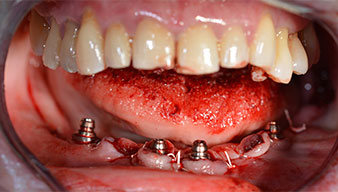

Ангулираните абатмънти (35°) са завити в имплантите, за да компенсират отклонението от дисталните импланти, така че в резултат профилът на разположение на всички импланти да е възможно най-перпендикулярен на нивото на захапката. Това е предпоставка за оклузално поставяне на временна и впоследствие на постоянна протеза (Фиг. 15 и 16).

След това е взет отпечатък и е определена захапката на пациента, за да може зъботехникът незабавно да започне изработването на временната протеза. Протезата е поставена в същия ден (Фиг. 17 и 18).

Светлината увеличава контраста в оралната кухина и подобрява визуалното възприятие. Обратният наконечник и S-11 прав наконечник на W&H са с външно охлаждане, което е голямо предимство по отношение на физиологичния разтвор, който достига точно, където трябва и може да бъде впоследствие редуциран, ако е необходимо. Правите и обратни наконечници могат да бъдат разглобени, което е силно препоръчително от гледна точка на хигиената и стерилизацията. Поставени са четири импланта SKY с размери 4.0 x 14 мм.